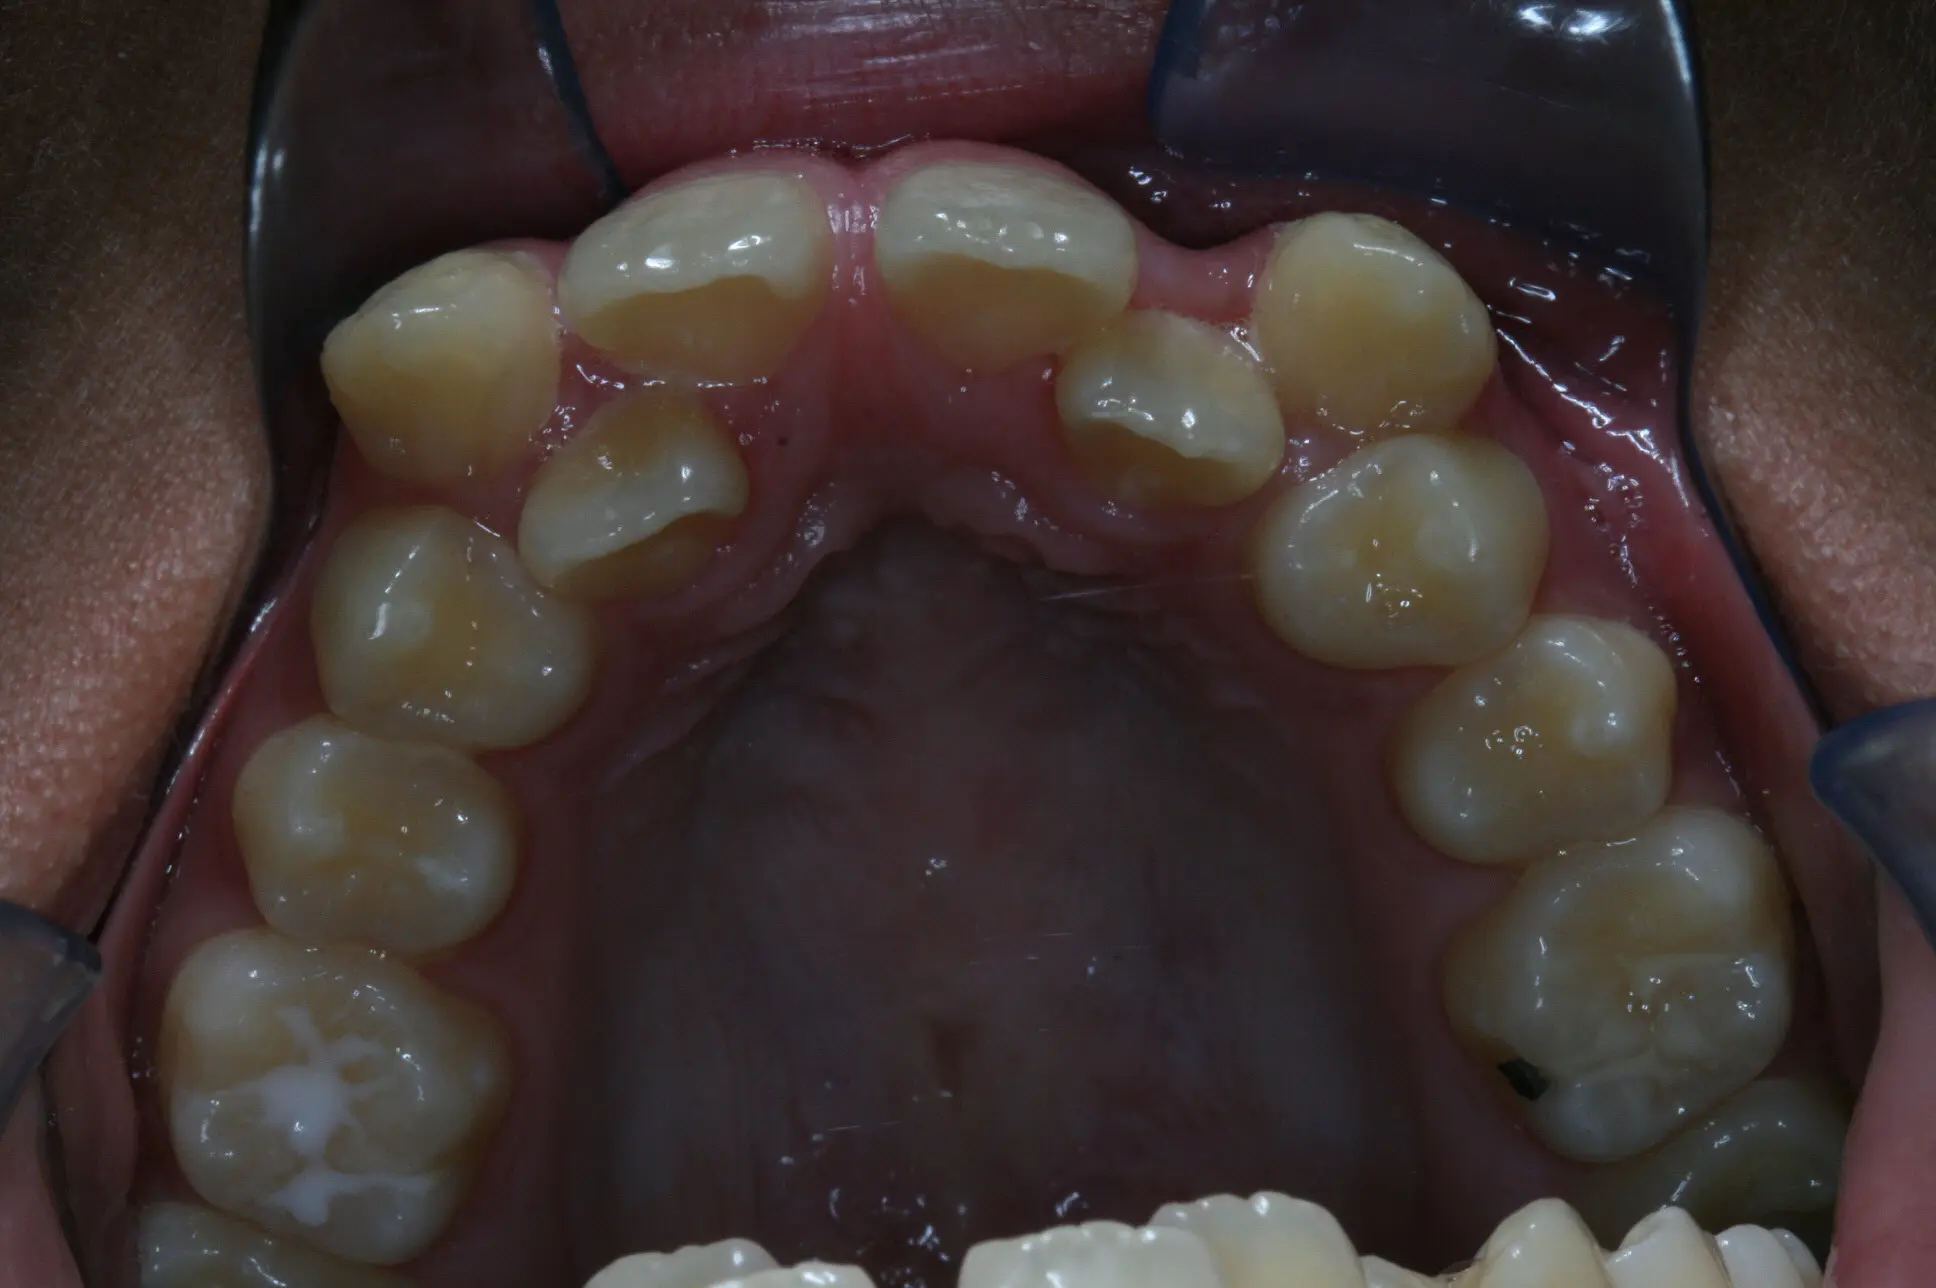

Invisalign Case in Progress – other orthodontist said Invisalign would not work. Invisalign always works in Dr. McCoy’s hands!

• Another orthodontist was talking jaw surgery and braces

• No surgery, just Invisalign by DesignTM with Dr. McCoy!

• Almost done. Just close some space and another happy patient is finished!

Before

After